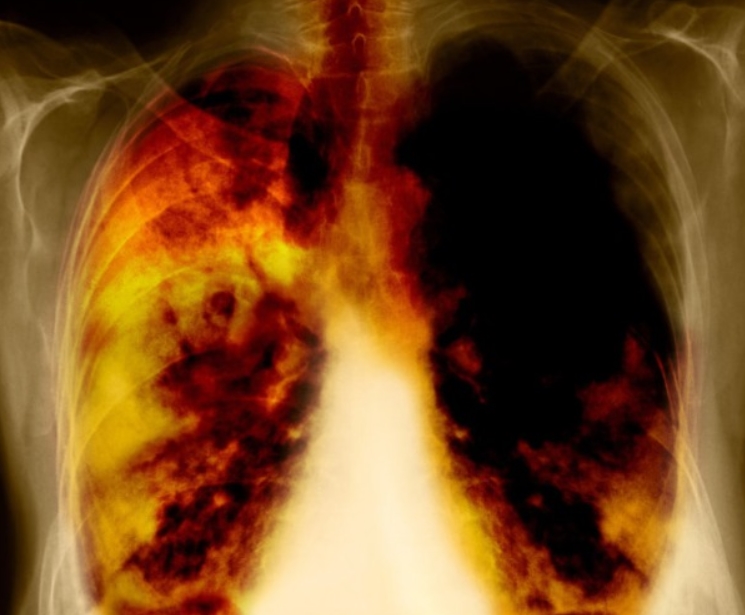

만성 폐쇄성 폐질환 증상 진단의 출발점은 폐 기능 검사입니다. 간단한 설문과 간이 측정으로 의심 대상을 고르고, 확진은 기도를 넓히는 약을 쓴 뒤 다시 측정해 내립니다. 경계에 걸리면 날짜를 달리해 반복 측정해 정확도를 높입니다. 흉부 CT는 허파가 얼마나 늘어났는지와 기도 벽이 얼마나 두꺼워졌는지를 보여 줍니다. 피와 가래 검사로 염증 성향을 살피면 주사 치료 대상인지도 가늠할 수 있습니다.